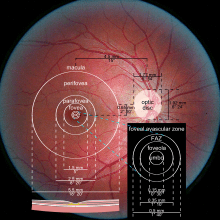

The macula or macula lutea (from Latin macula, "spot" + lutea, "yellow") is an oval-shaped pigmented area near the center of the retina of the human eye. It has a diameter of around 5.5 mm (0.22 in). The macula is subdivided into the umbo, foveola, foveal avascular zone (FAZ), fovea, parafovea, and perifovea areas.[1] After death or enucleation (removal of the eye) the macula appears yellow, a color that is not visible in the living eye except when viewed with light from which red has been filtered.[2] The anatomical macula at 5.5 mm (0.22 in) is much larger than the clinical macula which, at 1.5 mm (0.059 in), corresponds to the anatomical fovea.[3][4][5] The clinical macula is seen when viewed from the pupil, as in ophthalmoscopy or retinal photography. The anatomical macula is defined histologically in terms of having two or more layers of ganglion cells.[6] The umbo is the center of the foveola which in turn is located at the centre of the fovea.

Regions

- Fovea - 1.55 mm (0.061 in)

- Foveal Avascular Zone (FAZ) - 0.5 mm (0.020 in)

- Foveola - 0.35 mm (0.014 in)

- Umbo - 0.15 mm (0.0059 in)

Structures in the macula are specialized for high-acuity vision. Within the macula are the fovea and foveola that both contain a high density of cones (photoreceptors with high acuity).